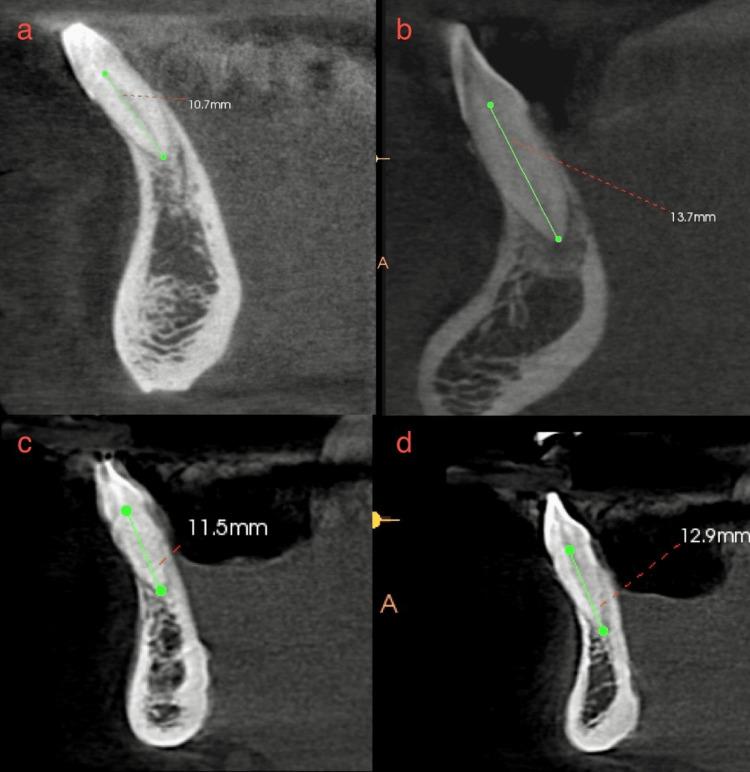

Aim Using two classifications, this study assessed root morphology and canal configuration and measured the Dentin thickness (DT) and canal shapes. Methods Cone beam computed tomography (CBCT) with 400 Mandibular Incisors was collected and assessed for the number, length, curvature of roots, number of canals, bifurcation level, configurations based on Vertucci's and Ahmed's classification, DT and canal shape at 3, 6, 9 mm from the apex. The collected data was subjected to statistical analysis with a level of significance at p<0.05. Results All samples had one root, averaging 12.769 ± 1.128 mm in central incisor (CI) and 13.044 ± 1.235 mm in lateral incisor (LI), with most roots being straight. Most samples had one canal in both teeth, with bifurcations most frequent in the middle third. The most frequent configuration was type 1 Vertucci or CI/LI by Ahmed, followed by type 3 or CI/LI. One sample, not classifiable under Vertucci, was classified as CI by Ahmed. The mean DT for CI was 3.18 ± 0.639 mm, 3.72 ± 0.671 mm and 4.43 ± 0.754 mm labiolingually and 1.578 ± 0.342 mm, 1.881 ± 0.374 mm, 2.283 ± 0.465 mm mesioditally at 3, 6, 9 mm from the apex, respectively. For LI, mean DT was 3.41 ± 0.916 mm, 3.90 ± 0.702 mm and 4.55 ± 0.746 mm labiolingually and 1.63 ± 0.322 mm, 1.981 ± 0.485 mm, 2.55 ± 0.470 mm mesioditally at 3, 6, 9 mm from the apex respectively, canal shape changed from oval to round, from apical to coronal. Conclusion Single canals were the most common, followed by two canals. The middle third of the canal had the most bifurcations. Vertucci type 1 or Ahmed's CI/LI  was the most commonly reported canal configuration, with one sample that could not be classified under Vertucci but could be classified using Ahmed classification. DT increased apical to coronal. The canal shape changed from oval to rounded, from apical to coronal.

目的 本研究使用两种分类方法评估牙根形态和根管形态,并测量牙本质厚度(DT)和根管形状。方法 收集400颗下颌切牙的锥形束计算机断层扫描(CBCT)图像,评估牙根的数量、长度、弯曲度、根管数量、分叉水平,根据Vertucci分类法和Ahmed分类法评估根管形态,测量根尖3、6、9 mm处的DT和根管形状。对收集的数据进行统计学分析,显著性水平为p<0.05。结果 所有样本均有一个牙根,中切牙(CI)平均长度为12.769±1.128 mm,侧切牙(LI)平均长度为13.044±1.235 mm,大多数牙根为直根。大多数样本的两颗牙均有一个根管,分叉最常见于中1/3处。最常见的形态为Vertucci分类法中的1型或Ahmed分类法中的CI/LI,其次是3型或CI/LI。有一个样本无法按照Vertucci分类法分类,但按照Ahmed分类法可归为CI。CI在根尖3、6、9 mm处的唇舌向平均DT分别为3.18±0.639 mm、3.72±0.671 mm和4.43±0.754 mm,近远中向平均DT分别为1.578±0.342 mm、1.881±0.374 mm和2.283±0.465 mm。LI在根尖3、6、9 mm处的唇舌向平均DT分别为3.41±0.916 mm、3.90±0.702 mm和4.55±0.746 mm,近远中向平均DT分别为1.63±0.322 mm、1.981±0.485 mm和2.55±0.470 mm,根管形状从根尖向冠方由椭圆形变为圆形。结论 单根管最为常见,其次是双根管。根管的中1/3处分叉最多。Vertucci 1型或Ahmed的CI/LI是最常报道的根管形态,有一个样本无法按照Vertucci分类法分类,但可按照Ahmed分类法分类。DT从根尖向冠方增加。根管形状从根尖向冠方由椭圆形变为圆形。